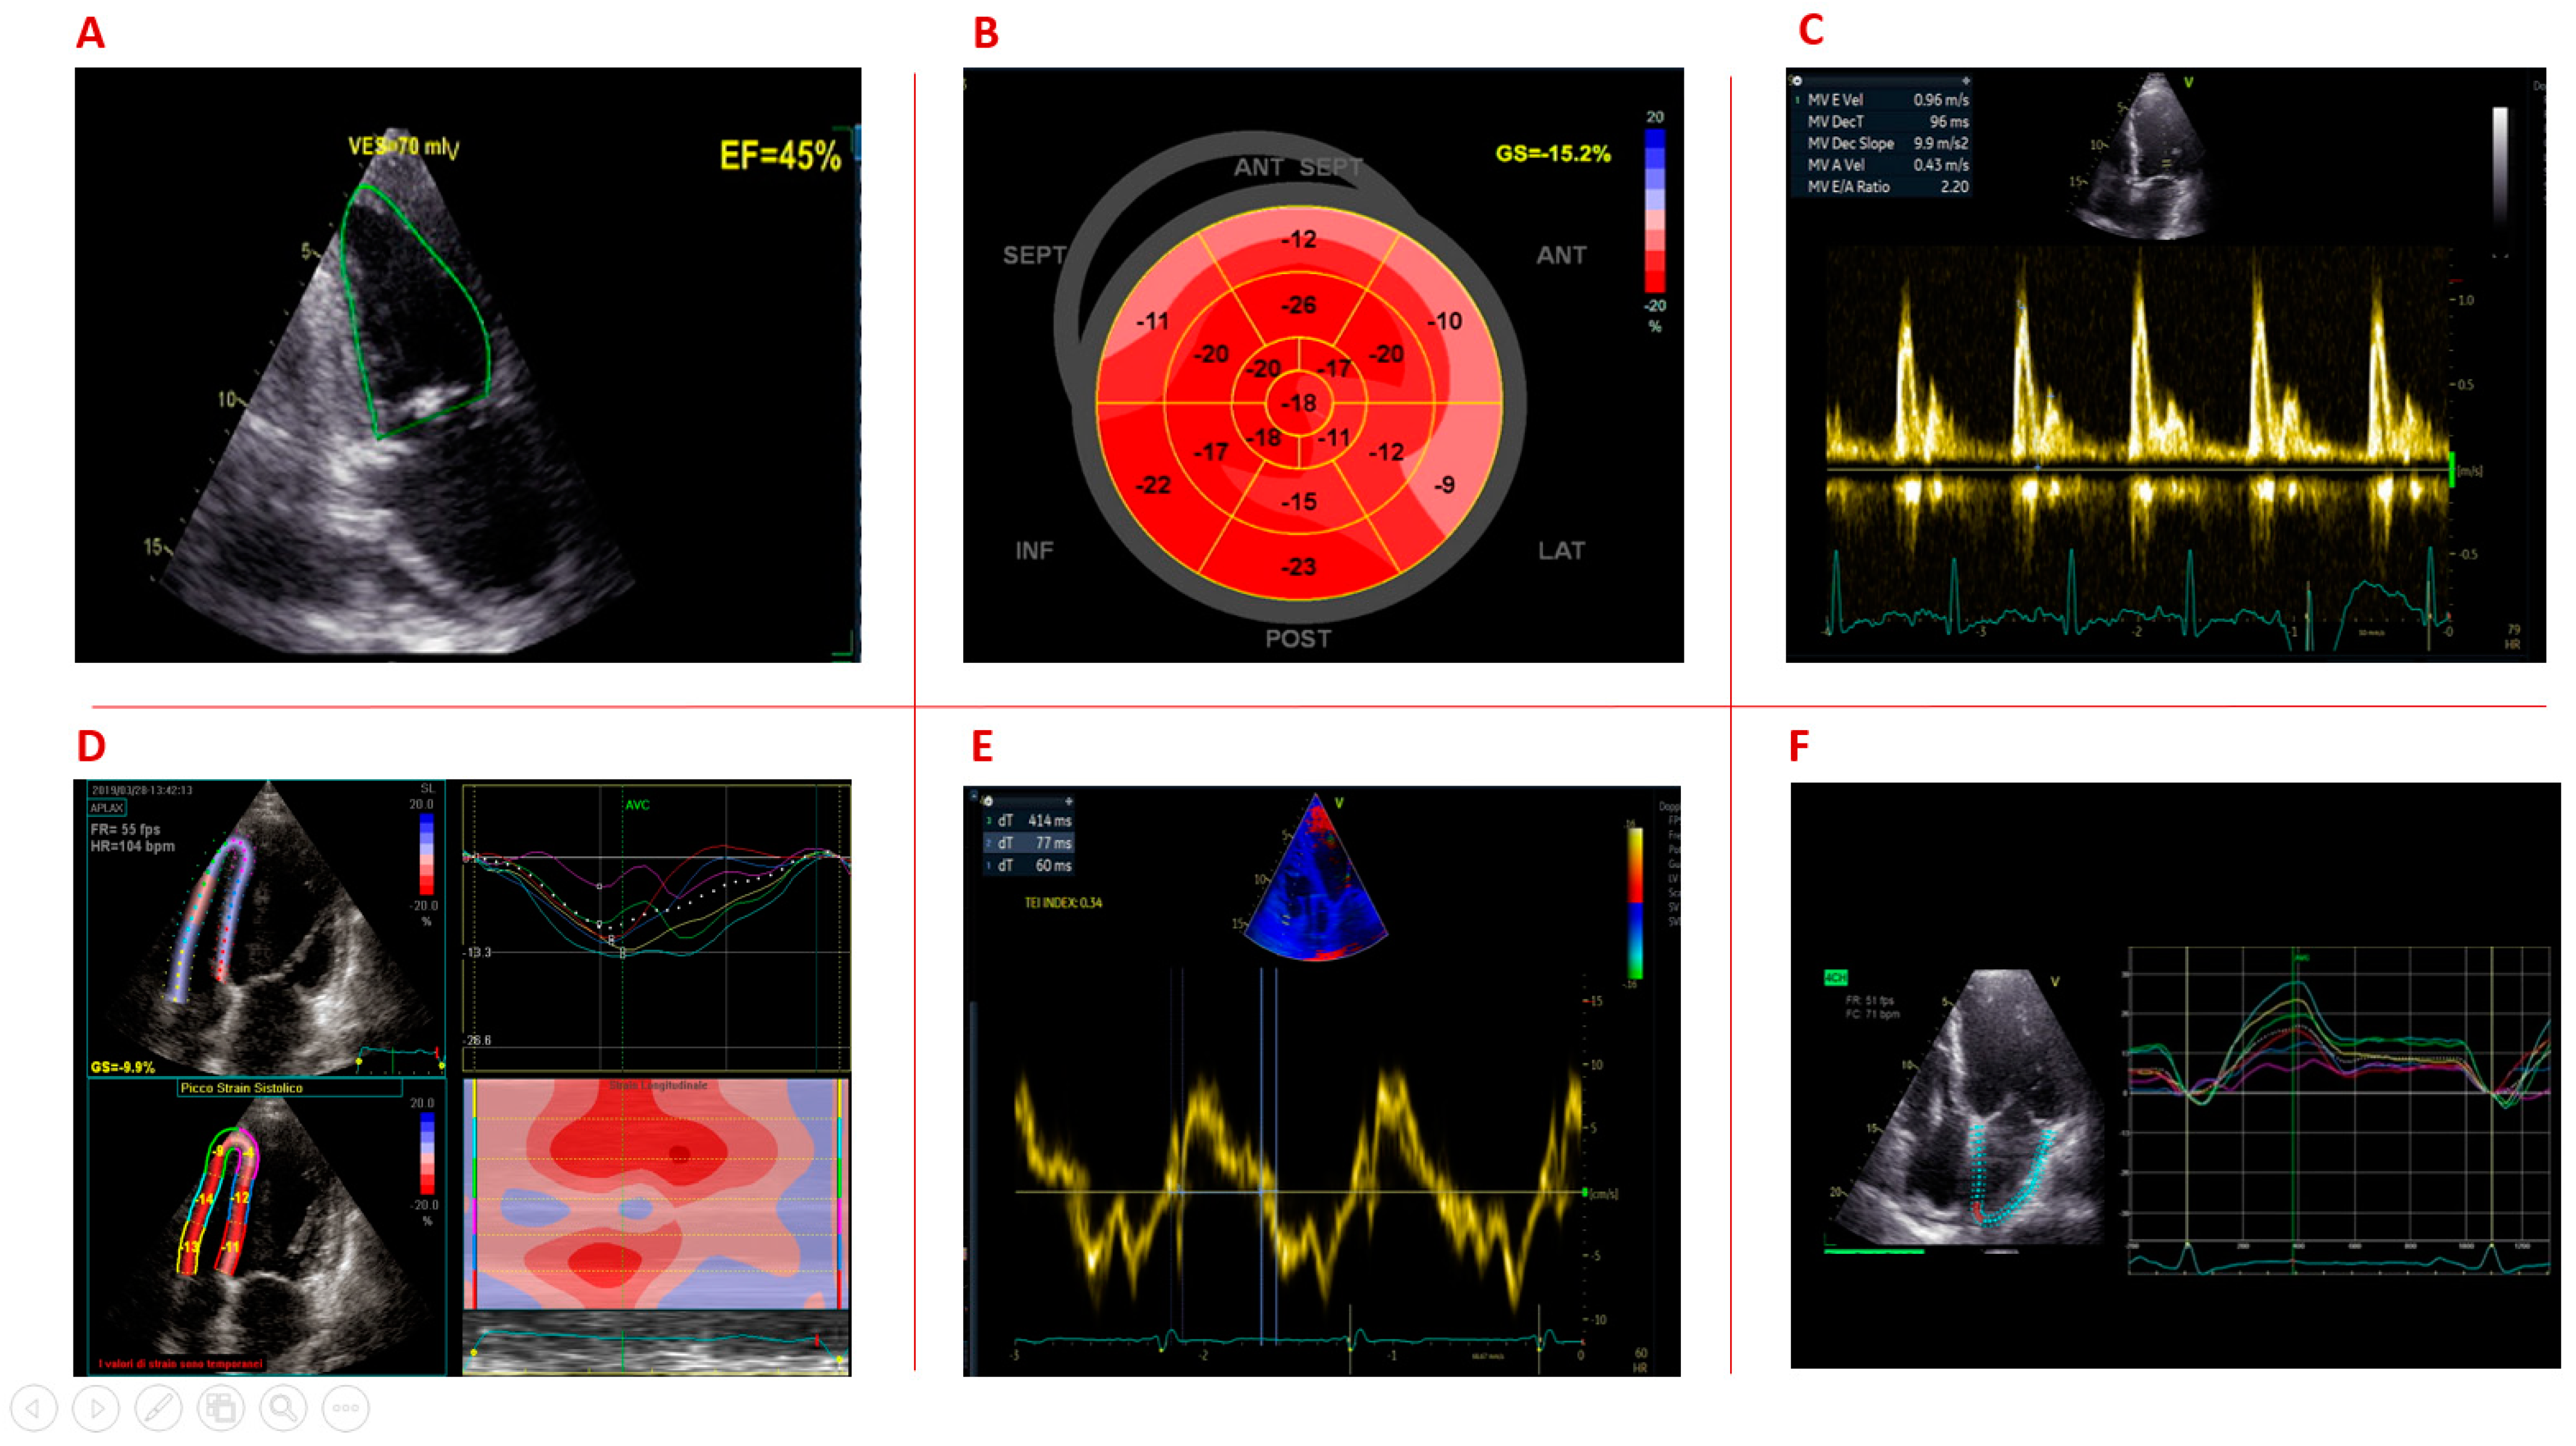

1.1. Left Ventricular Systolic Dysfunction

1.2. Left Ventricular Strain

1.3. Left Ventricular Diastolic Dysfunction

1.4. Right Ventricular Function

1.5. Left Atrial Function

| Russo [20] | 2020 | Systematic review | 876 | 42.68 | - | LVEF < 55% | The prevalence of LVEF < 55% was 13.8%. |

| Garcia [29] | 2017 | Prospective study | 33 | 38.2 ± 12.9 | 33 | LV GLS | DM1 patients exhibited significantly altered LV GLS, particularly at the apex (−20.0 ± 3.3 vs. −22.7 ± 3.1; p < 0.001), as compared with controls. |

| Garcia [13] | 2017 | Prospective study | 46 | 40 [29–49] | - | LV GLS | LV GLS (cut-off value of −17.2%) predict cardiovascular events, regardless LVEF. |

| Guedes [36] | 2017 | Observational study | 25 | 36.9 ± 16.0 | 25 | LA and LV GLS | LA longitudinal strain is significantly decreased in patients with DM1 compared to controls (22.85 ± 5.06 vs. 26.82 ± 5.15 p = 0.008). |

| Petri [28] | 2014 | Cross-sectional study | 129 | 44 (15) | - | GLS | The prevalence of abnormal GLS was 21.7% Abnormal GLS was above −15.9%; 60% had preserved LVEF> 50%. |

| Sousa [27] | 2013 | Case–control study | 25 | 36.7 ± 12.5 | 13 | GLS | DM1 patients showed a lower GLS than controls (−16.6 ± 3.6% vs. −18.7 ± 1.8%, p = 0.022). GLS correlates with PR interval duration. |

| Wahbi [26] | 2011 | Case–control study | 39 | 37.5 ± 12.1 | 39 | LV GLS | Speckle tracking GLS was able to identify LV contractility abnormalities in DM1 patients with normal LVEF. DM1 patients showed a lower apical 4 chambers GLS compared to controls (−17.8 ± 2.5 vs. −19.2 ± 2.3 p = 0.01), which significantly correlated with PR interval. |